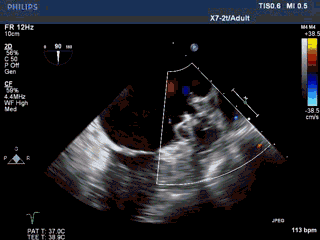

手术过程—PASS原则,残余分流

Seal:封堵器贴壁良好,各切面无残余分流。